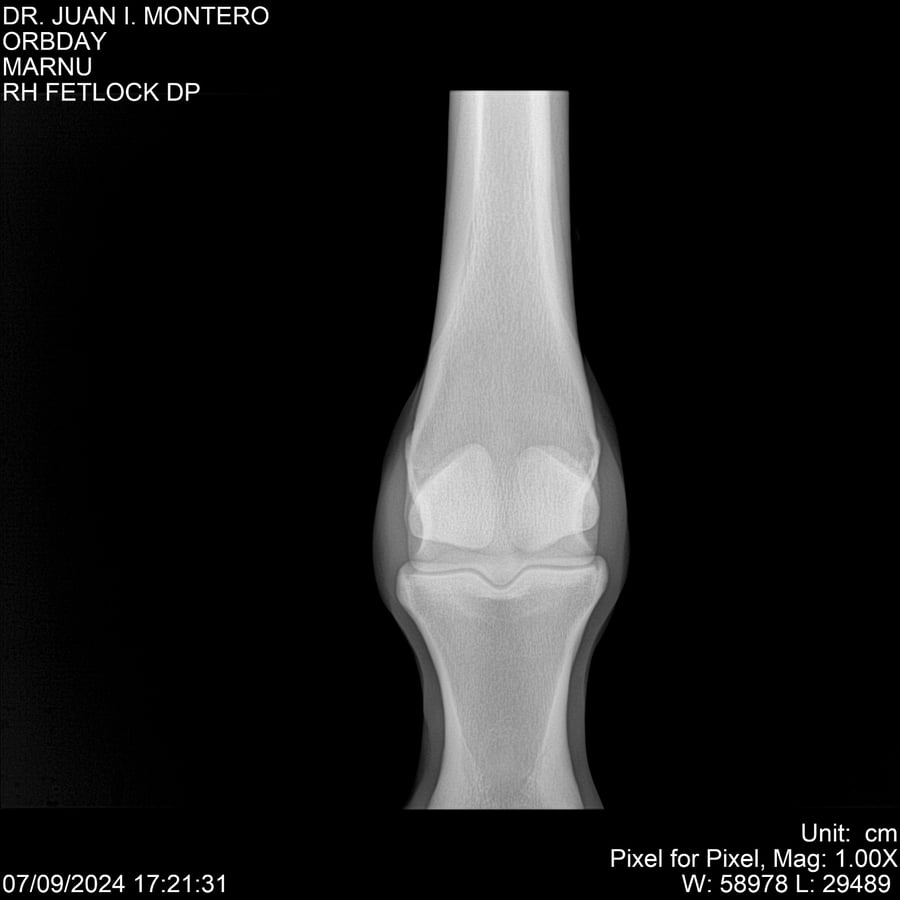

• Empresa: Abelenda N. R., Walter Hugo